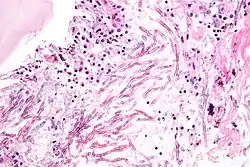

Las micosis (del griego μυκος, hongo) son las infecciones causadas por hongos a animales o vegetales.[1]

Algunas micosis son afecciones oportunistas que prosperan ante una baja de las defensas del sistema inmune del sujeto afectado.[2] Tal baja puede ser causada por estrés, estados psíquicos de ansiedad o depresión, por el retrovirus del VIH-Sida o por ciertos tratamientos quimioterápicos, entre otros factores. Un ejemplo típico de micosis oportunista es la candidiasis.

La micosis es una enfermedad infecciosa que afecta los tejidos de la piel debido a la presencia de hongos. Estos hongos tienden a proliferar en áreas del cuerpo donde se acumula la humedad, como la zona inguinal, los genitales, las uñas de las manos y los pies, el cuero cabelludo, entre otras.